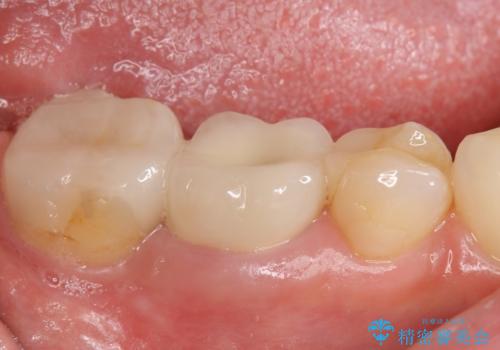

- たまに疼くことがあると他院を受診したところ抜歯を勧められたが、歯を残せないものかと当院にいらっしゃった方の症例です。

診査の結果抜歯の必要性はなさそうだったため再根管治療を行い、その後オールセラミッククラウンによる補綴を行いました。

今回用いたオールセラミッククラウンはジルコニアフレームという白い素材の上にセラミックを盛っているため、審美性が非常に高いのが特徴です。

また、ジルコニアは人工ダイヤモンドの材料にも使われているほど高い強度を持っており、そのためオールセラミッククラウンは審美性だけでなく、奥歯やブリッジの補綴も可能とするクラウンです。